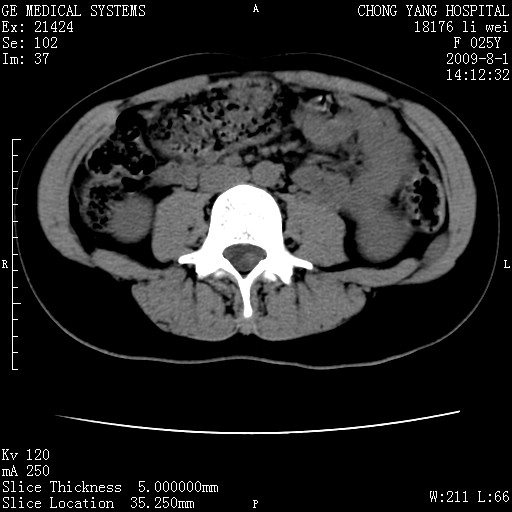

以下是引用pujunzhi在2009-8-1 20:23:00的发言:[br]胸椎旁及背部肌间良性病变,范围广,边界清,沿肌间生长,考虑淋巴管瘤、血管瘤,建议增强扫描。

以下是引用拾荒者在2009-12-30 21:45:00的发言:[br]ct21383:神经纤维瘤病( nf) [br] [br] 神经纤维瘤病。四肢都有,影响美观,四肢上的手术了。[br] [br] [br]谢谢!